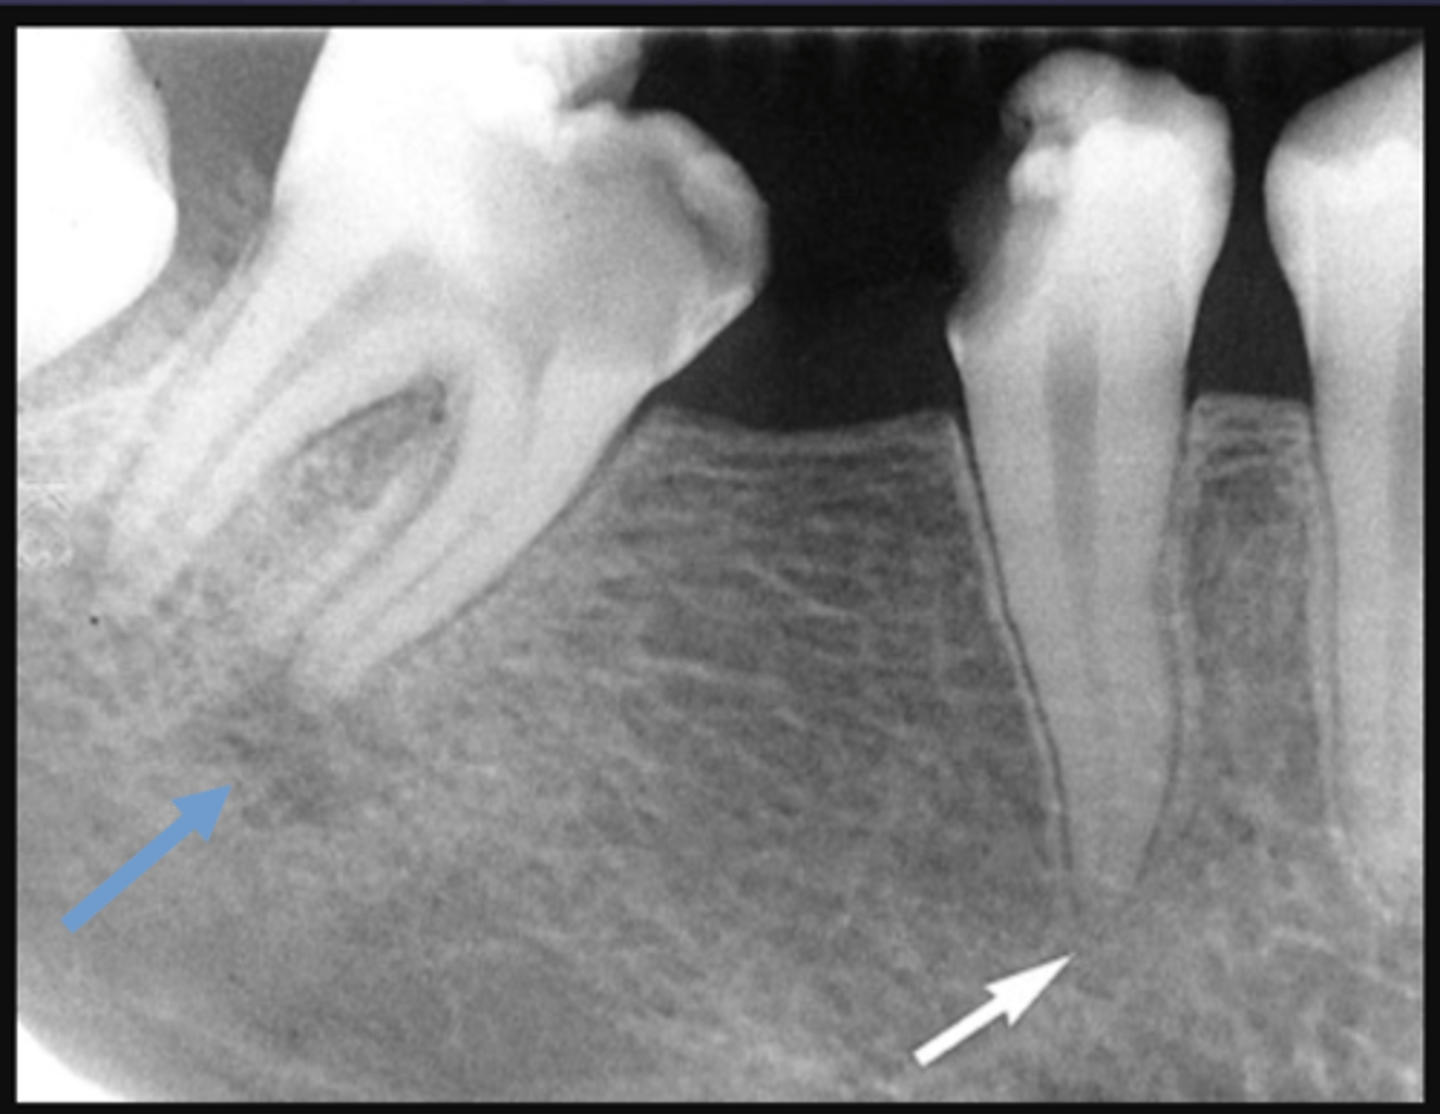

The white arrow is showing what stage of lesion?

early (involving pulp, no changes in bone)

The blue arrow is showing what type of lesion?

chronic (loss of lamina dura, apical radiolucency and surrounding sclerotic bone reaction)